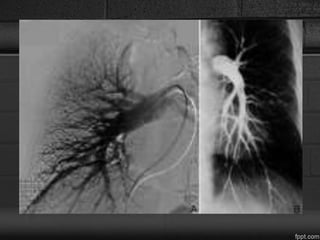

Pulmonary angiography

• Vascular tortuosity, webs, bands, stenoses, “pouching defects,”

and abrupt vascular cutoffs or occlusions.